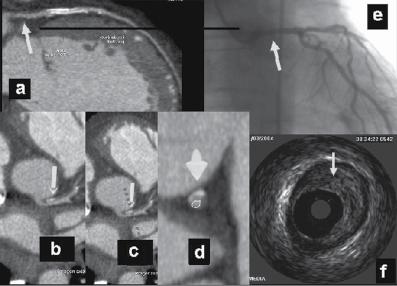

Figure 1.1 (A) Normal case: coronary angiography (left) and three‐dimensional CTA (right) showing normal left anterior descending (LAD, arrow) and left circumflex (LCX) coronary arteries. The latter is partially covered by the left appendix in CTA. (B) Normal case: coronary angiography (left) and CTA (right) showing a normal dominant right coronary artery (RCA). (C) An 85‐year‐old man with atypical chest pain: (a) Maximal intensity projection (MIP) of CTA with tight mid‐LAD stenosis that correlates perfectly with coronary angiography (b). (D) Similar case as (C) but with the stenosis in the proximal RCA. (a–d) CTA and (e) coronary angiography. (E) A patient with tight stenosis in the LCX before a bifurcation. (a) and (b) CTA and (c) coronary angiography. (F) These images show that CTA may also demonstrate the presence of stenosis in distal vessel branches, in this case in the posterior descending branch of the RCA. (a–b) CTA and (c) coronary angiography. (G) These images show that CTA (a, b) may delineate the length of a total occlusion and visualize the distal branches (see arrows in (b)). Collateral flow from the LAD to the RCA may be better visualized with CTA than with conventional coronary angiography (c: here only the RCA is shown). (H) A 42‐year‐old patient with a stent implanted in the LAD six months before. The patient complained of atypical chest pain and underwent CTA. The MIP images of CTA (a–c) show no significant restenosis, but some plaque formation in the left main trunk (d, circle) that was not well seen in coronary angiography (e). The degree of luminal obstruction by the plaque can be exactly measured by intravascular ultrasound (IVUS) (f). The ECG showed mildly inverted T waves in V1–V3 during follow‐up (see Plate 1 in color plates).

Figure 1.1 (Continued)

(d)

(e)

(f)

1.1 (Continued)

(h)

Figure

intervention (PCI) (Figure 1.1). CTA may provide additional diagnostic information for clinical decision‐making in contemporary stable chest pain patients with intermediate pre‐test probability for IHD (Hoffmann et al. 2017). In additional to narrowing, CTA can provide information on coronary distribution, including abnormalities in the origin and course of the arteries, and presence of coronary aneurysms. However, the accuracy of assessing the severity of coronary stenosis in highly calcified lesions and within stents is reduced.